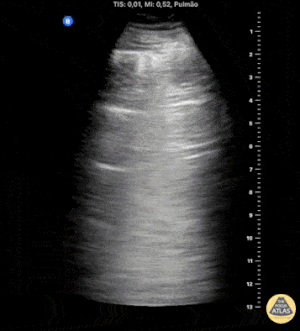

M-mode kullanımı

Pnömotoraks değerlendirmesinde M-mode da kullanılabilir.

Aynı pencerede M-mode kaydı alınır:

-

Lung sliding varsa (pnömotoraks yoksa)

Plevral hat seviyesinde belirgin bir ayrım görülür ve bu görünüm “seashore sign” (kumsal belirtisi) olarak adlandırılır.

Lung sliding yoksa (pnömotoraks şüphesi)

Üstten alta kadar paralel çizgiler görülür ve bu görünüm “barcode sign” (barkod belirtisi) olarak adlandırılır.